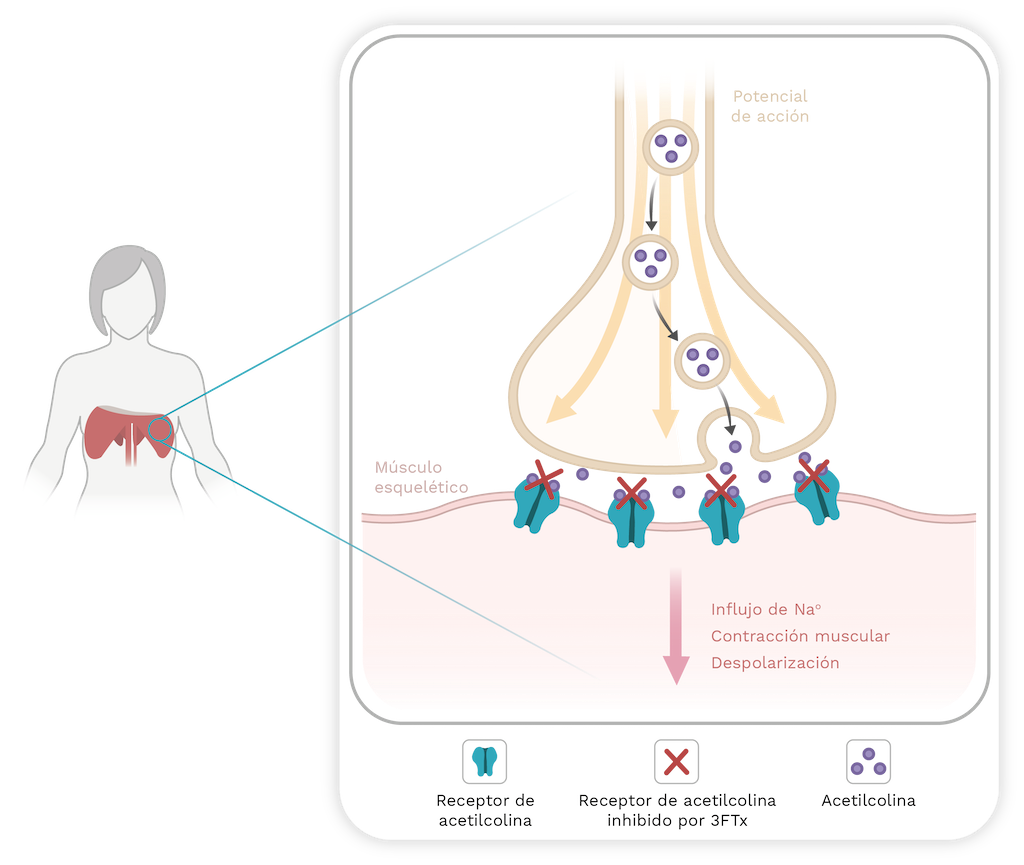

La variabilidad del veneno se produce debido a las trayectorias evolutivas de las serpientes venenosas, así como a la especialización de algunas de sus toxinas. Por ejemplo, los venenos tanto de las familias Elapidae y Viperidae están dominados por dos o tres familias de proteínas: fosfolipasas A2 (PLA2) y toxina de tres dedos (3FTx) para los elápidos, y metaloproteasas (SVMP), PLA2 y serino proteasas (SVSP) para los vipéridos. En promedio, estas familias de proteínas constituyen el 83% y el 67% del proteoma del veneno de elápidos y víboras, respectivamente [24].

Los venenos de serpientes de la familia Elapidae son principalmente neurotóxicos, mientras que los de la familia Viperidae inducen coagulopatías, hemorragias y daños tisulares locales [25,26]. Esto se debe a la prevalencia de las proteínas 3FTx y PLA2 en el veneno de elápidos que pueden causar debilidad similar a la miastenia gravis [27]. Esta debilidad puede afectar a cualquier músculo; y si el bloqueo neuromuscular afecta a los músculos de la respiración, puede provocar la muerte [26,27]. Por otro lado, el veneno de vipéridos tiene efectos principalmente hemotóxicos y miotóxicos. Los agentes identificados en el veneno de las víboras incluyen proteinasas similares a la trombina que provocan coagulopatía [28], hialuronidasas que alteran las matrices extracelulares, fosfolipasas A2 que causan inflamación local y dolor [29], y metaloproteasas que contribuyen a la hemorragia [30,31]. El resultado es una destrucción local del tejido empeorada por el efecto coagulopático [26].

Neurotoxicidad

La neurotoxicidad presináptica o β-neurotoxicidad es otro efecto relevante observado en algunas mordeduras de serpientes. Por ejemplo, las infligidas por serpientes cascabel sudamericanas (Crotalus durissus) y las serpientes coral (especies de Micrurus; ver Capítulo 9) [113]. Las toxinas responsables de este efecto se denominan β-neurotoxinas, y sus estructuras poseen una, dos, tres y hasta cinco subunidades que pueden interactuar mediante enlaces covalentes o no covalentes. Una de sus subunidades es una PLA2 catalíticamente activa [118]. La toxicidad surge de la inhibición de la liberación de acetilcolina (Ach), lo que lleva a una parálisis flácida de los músculos respiratorios, incluido el diafragma. La inhibición de la liberación de Ach ocurre en tres pasos: primero, hay una ligera inhibición transitoria de la liberación de Ach que está relacionada con la unión de PLA2 a la membrana presináptica; segundo, hay un aumento significativo en la liberación de Ach; y finalmente, hay una inhibición sostenida de la liberación de Ach [112,119,120].

Sin embargo, el mecanismo por el cual las β-neurotoxinas son transportadas a las células nerviosas sigue siendo desconocido. Estas toxinas podrían ser internalizadas a través de poros generados después de la hidrólisis de la membrana presináptica, o las proteínas podrían usar la endocitosis de vesículas sinápticas como vehículo para entrar en las células nerviosas [125]. Una vez que la PLA2 entra en la neurona, se une a ciertas proteínas como la calmodulina, la proteína disulfuro isomerasa y proteínas de nombre 14-3-3; pero las implicaciones específicas para el modo de acción de la toxina no son claras. De manera similar, la calmodulina estabiliza la capacidad de la PLA2 para hidrolizar glicerofosfolípidos [126]. Además, las proteínas 14-3-3 desempeñan un papel importante en la dirección de las PLA2 a las vesículas sinápticas para llevar a cabo su actividad catalítica y posteriormente inhibir la endocitosis de vesículas [127]. En última instancia, estos eventos contribuyen a la falla de la unión neuromuscular, lo que resulta en la inhibición de la liberación de Ach y la posterior parálisis flácida [118–121,128,129] (Figura 10).

La crotoxina (CTX) es una β-neurotoxina derivada de Crotalus durissus, la serpiente cascabel sudamericana [138]. Consiste en una subunidad básica PLA2 conocida como CB y una subunidad ácida llamada crotapotina (subunidad A o CA). Esta última actúa como chaperona, guiando la subunidad CB a las células diana (motoneuronas) y evitando la unión de la PLA2 a sitios no específicos [131,132]. Además, CA aumenta la actividad neurotóxica de CB pero disminuye su actividad enzimática [133,134]. Por lo tanto, el complejo de crotoxina es responsable de la neurotoxicidad observada en el envenenamiento por la serpiente cascabel colombiana. Otras toxinas encontradas en venenos de especies de Colombia, clasificadas como β-neurotoxinas, incluyen las PLA2 aisladas de los venenos de las serpientes coral Micrurus mipartitus y M. dumerilii [135].